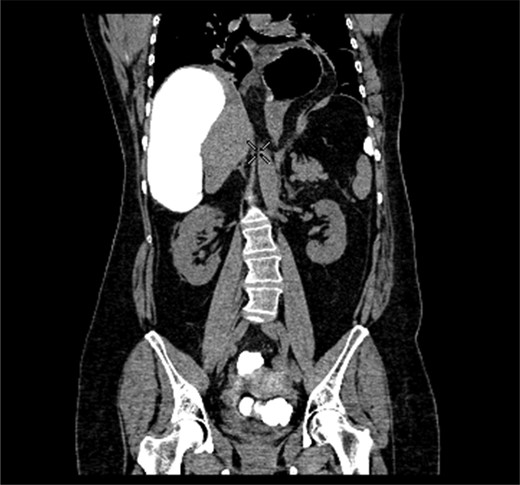

A 58-year-old female with a past medical history of a large intrathoracic hiatus hernia presented to her general practitioner and was subsequently referred to our surgical department with symptoms of sudden onset severe epigastric pain associated with vomiting and abdominal distension. Her abdomen was generally tender, maximally in the epigastric region, although she was not peritonitic. The admission erect chest radiograph showed a large hiatus hernia and an elevated right hemidiaphragm with a large loop of distended bowel (Fig. 1). Subsequent computed tomography (CT) scan demonstrated an almost completely intrathoracic stomach with a degree of volvulus, and the liver medially displaced by a loop of large bowel felt to be caecum (Fig. 2). Since the patient remained otherwise well, bidirectional endoscopy was performed, and given that a volvulus point could not be identified and the ileocaecal junction was not identified, contrast studies were requested (Figs 3–5) which demonstrated an incomplete obstruction caused by a volved caecum rotated anteriorly and cephalad.

CT coronal section demonstrating caecum medially displacing the liver and causing an upward pressure on the right hemidiaphragm.

Coronal section of contrast-enhanced CT demonstrating contrast filling upwardly displaced caecum.

Axial section of contrast-enhanced CT demonstrating ‘whirl sign’ at the point of volvulus.

Radiological imaging is useful in diagnosing caecal volvulus. Rosenblat et al. [8] found that CT findings of whirl, ileocaecal twist, transition points, X marks the spot and split wall have high specificity for caecal volvulus. Additionally, they found that the absence of distal colonic decompression made the diagnosis of caecal volvulus unlikely. Diagnostic confusion may exist between sigmoid and caecal volvulus; however, the location of the mesenteric twist (CT whirl sign) is highly accurate in distinguishing the two [9]. This whirl sign, as first published by Fisher [10], describes ‘swirling strands of soft tissue attenuation within a background of fat attenuation and gives the appearance of a hurricane on a map’. Barium enema has been historically used to confirm the presence of a volvulus, assess the distal colon and may also have a therapeutic effect [3].